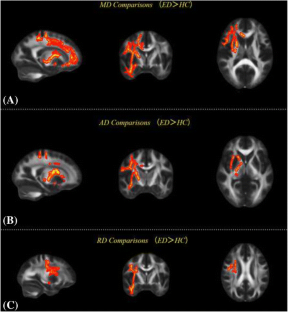

Compared to healthy control subjects, VED patients showed significantly decreased cortical volumes in the left postcentral gyrus and precentral gyrus, while only the right middle temporal gyrus showed a significant increase in cortical volume. Increased axial diffusivity (AD), radial diffusivity (RD) and mean diffusivity (MD) values were observed in widespread brain regions. Certain regions of these alterations related to VED patients showed significant correlations with clinical symptoms and disorder durations. Machine learning analyses discriminated patients from controls with overall accuracy 96.7%, sensitivity 93.3% and specificity 99.0%.

Cortical volume and white matter (WM) microstructural changes were observed in VED patients, and showed significant correlations with clinical symptoms and dysfunction durations. Various DTI-derived indices of some brain regions could be regarded as reliable discriminating features between VED patients and healthy control subjects, as shown by machine learning analyses.